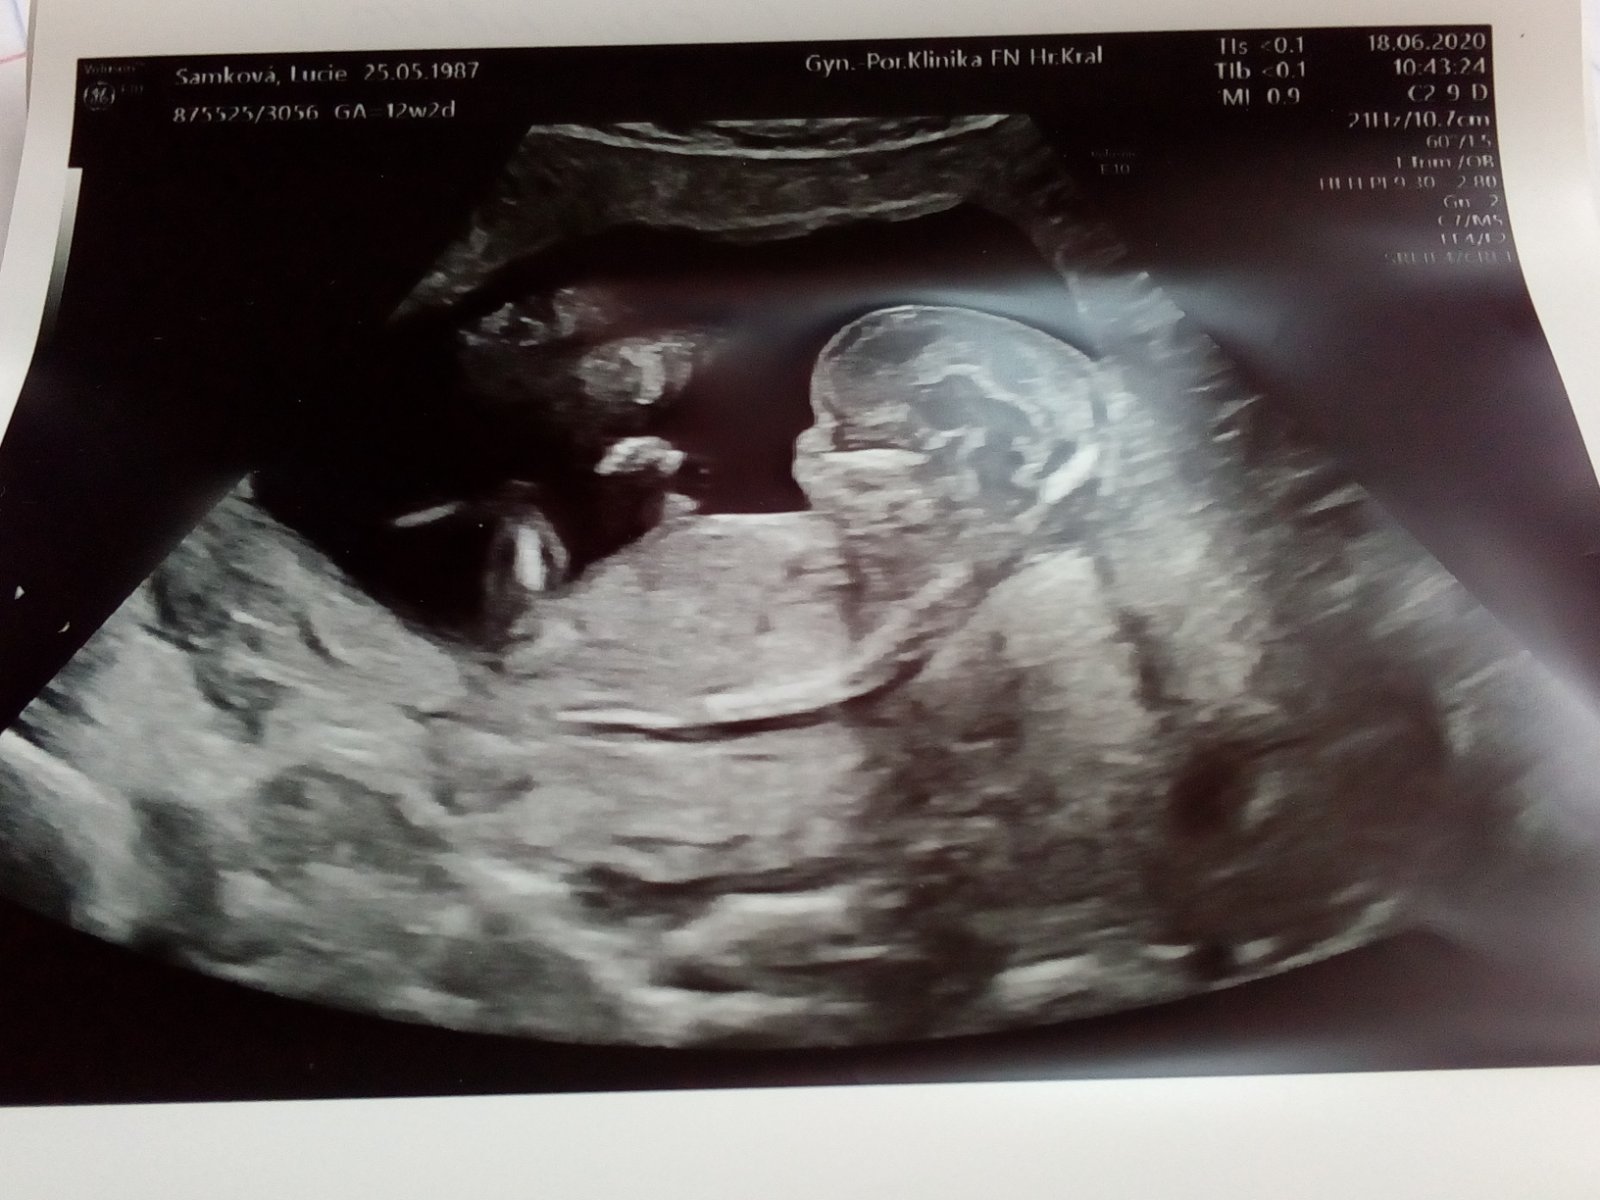

Je to holčička nebo chlapeček? Foto ultrazvuku

@almidrob2539 Bohužel tady vidíme jen zadeček miminka, jinou fotku nemáte?

@rennye me domtor tvrdil ze je zepredu a ze ma rostazene nohy a ze az tam bude mít pohlavi tak doufa ze to ukáže stejně tak hezky jako tady ba fotce . Jedna moje známá mi poslala místo jde prý vidí kavove zrno

@almidrob2539 To už by mělo jít vidět hezky ve 13 tt, to už by musel vidět i doktor, kdyby tam to kávové zrno bylo vidět, já tam nevidím bohužel nic, a starší fotku z boku máte?

@almidrob2539 To je nějaká kustka, kazdopadne kávové zrno to určitě není. To bývá vidět přímo mezi nozkama, tady jsou záda. 🙂 na fotce to bohužel nejde vidět. A pokud neviděl doktor, my tady těžko uvidíme.

@almidrob2539 To je pořád ta samá fotka, ale zvětšená. Holka to být může, je to více pravděpodobné, ale jistá bych si tím nebyla, je to špatně vidět. Takové fotky mám i od kluků 😂.

@ltaborikova Holcicka 😘. Nějak i podle tvaru hlavičky mi to připadá. Na druhou stranu já jsem mela taky podobnou fotku a byl to nakonec chlapeček. Ale bylo to brzy 12+0. Vy to mate o tyden pozdeji a tam by to mělo byt uz zřetelnější...